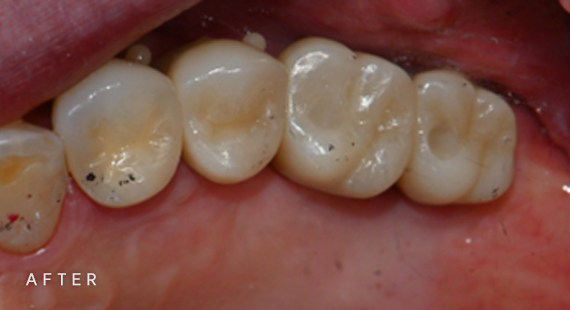

충치치료